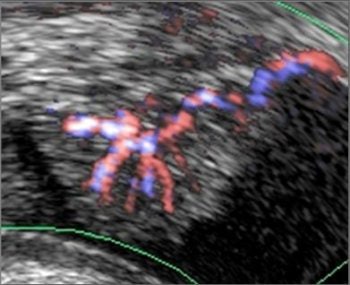

Freehand scanning was used for 3D data acquisition, and surface rendering and multiplanar reconstruction for 3D data analysis. Power Doppler ultrasound was used to differentiate the extent of infiltration. The criteria for staging were based on the vascularity of the tumor's basement. The gold standard was the histomorphology results.

| Power Doppler ultrasound criteria for staging vascularity of the tumor basement. Above, submucosal vessels; second, half muscle wall vascular. Below, whole muscle wall vascular; second image, few vessels in the perivesical walls; third image, massive flow in the perivesical fat. Images courtesy of Dr. Veronika Gazhonova, Russian President Medical Center and Russian State Medical University. |